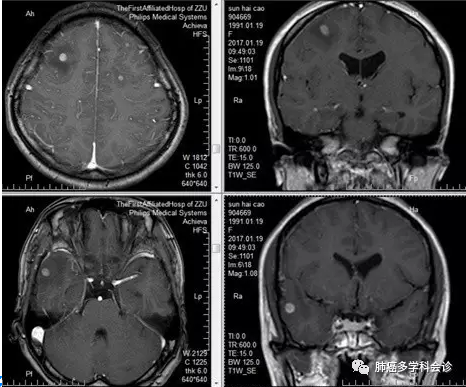

骨髓穿刺示:骨髓增生减低:粒系增生减低,红系增生减低,浏览全片未见巨核细胞,血小板散在可见,浏览全片偶见聚集血小板。浏览两张髓片可见成团分类不明细胞,其胞体偏大,圆形、类圆形,细胞边界不清,胞浆染蓝色。见下图: